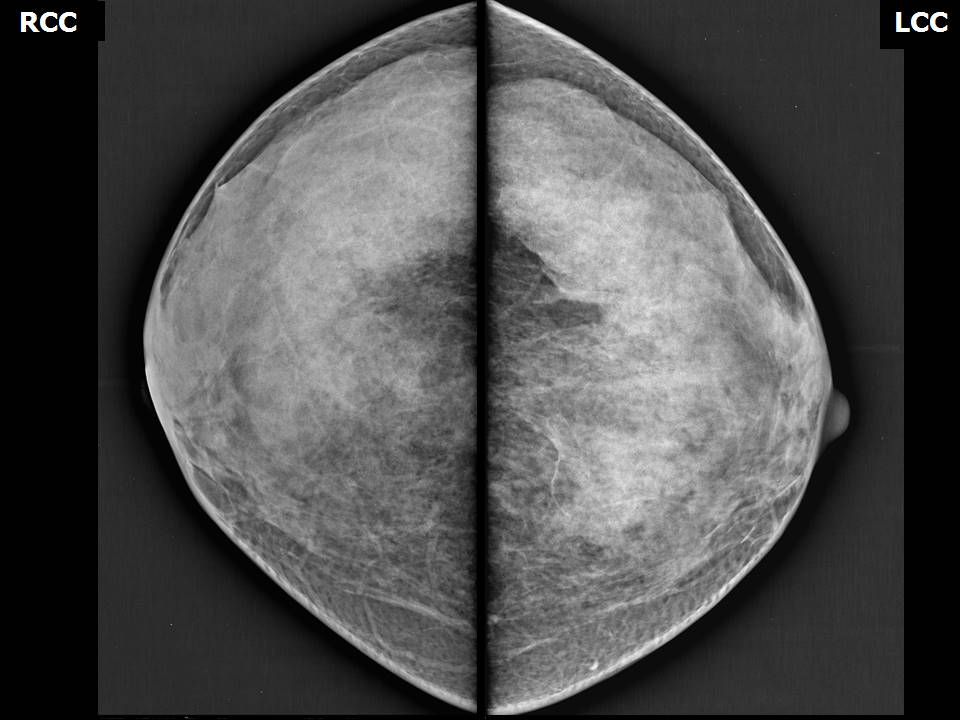

Аномалии молочной железы: медицинские примеры и визуализация

Раздел: Мудрость в деталях